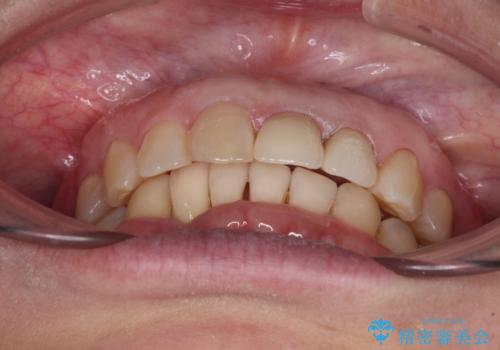

- 下顎前歯が抜けそうとのことで来院された患者様です。

初診の状態ではすぐにでも抜けそうな状態で、インプラントによる補綴治療を行うこととしました。

インプラント治療に際し、前歯の叢生に対する矯正治療を提案したところ、興味を持たれたので、インビザライン・ライトによる矯正治療を行うこととしました。

抜歯後にスペースができると恥ずかしいため、抜歯した歯を接着剤で固定した上で矯正治療を行い、その後インプラントやオールセラミッククラウンの装着を行うこととしました。